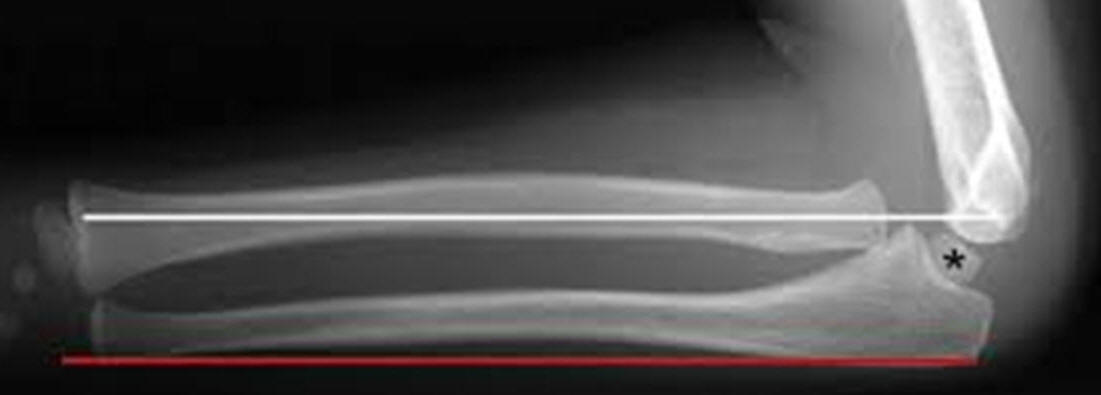

Undersiden af ulna skal være helt lige:

Ved en bowing ulna ses ofte caput radii luksation: